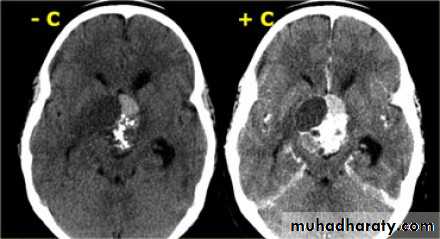

Glioma

Comments primary interracial tumor , vary greatly in malignancy , have many names depending on the histological type :astrocytoma

oligodendroglioma both of them are well differentiated slowly growing t.

gliobtastoma multiforme G IV highly malignant t. named also as butterfly G. arise from the anterior or posterior aspect of the corpus callosum , extend & spread to both cerebral hemispheric sides

Low grade G. I well or ill defined lesion iso dence to the brain tissues , not associated with oedeme , no Enhancement , no associated Hemorrhage , necrosis .

From G II , III, various previous finding

IV( glioblastoma multiforme ) are highly malignant have all previous mentioned features .